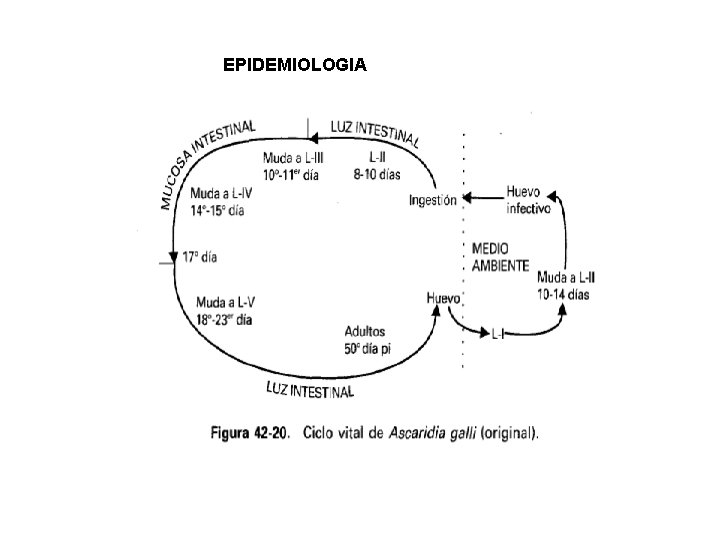

EPIDEMIOLOGIA